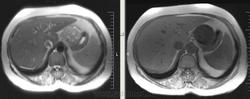

Интересные брюшные полости пошли в последнее время. Женщина, 1941 г.р. Оформлялась на операцию (по глазам), прошла УЗИ, после чего направили к нам. Жалобы только на глаза и суставы, на брюшную полость никаких. 2 года назад делала ФГС - все в порядке было. Коллеги, подскажите, пожалуйста, откуда растет эта штука? Из брюшины? Или из желудка? Или еще откуда-то?

Как-то очень близко к желудку прилежит, даже местами четко граница не прослеживается.

Согласен с Алексеем Станиславовичем. Опухоль связана со стенкой желуда, что видно на сканах 76, 77, 110, 111, стенка желудка истончена, накапливает контраст. На лейомиому в чистом виде опухоль не очень похожа, как я её себе представляю, зоны деструкции, кровоизлияния, может быть малигнизированная если. Но выглядит довольно доброкачественно в плане операбильности, имеет капсулу (не в месте контакта с желудком). Мне недавно попадалась опухоль точно такой же локализации, но имела совершенно другую структуру, прилежала к брюшине без явных признаков прорастания её. Пациентка врач, я думаю узнаю гистологию у неё, но та выглядела злокачественной.